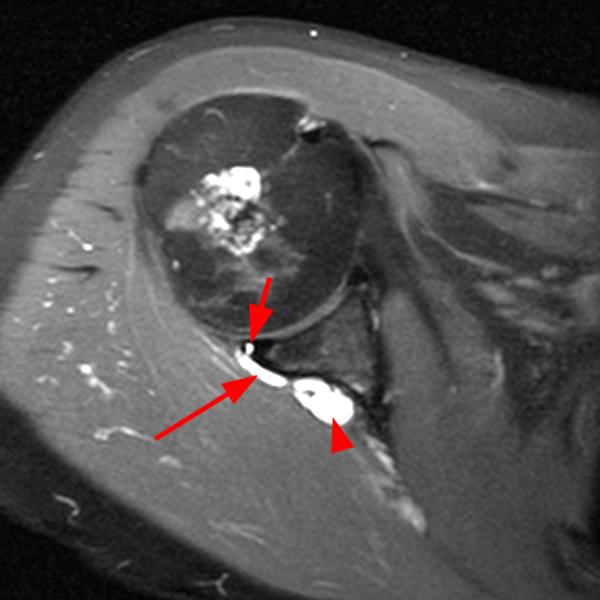

Shoulder Cysts Mri

From mavink.com

Shoulder Cysts Mri Back Shoulder Cyst A paralabral cyst, or ganglion cyst, is a fluid collection arising from the shoulder’s ball and socket joint. Let’s start by looking at the four most common causes of a lump on the back of your shoulder and how to treat them. A sebaceous cyst on the shoulder, aka epidermoid shoulder cyst is a small sac filled with keratin, a. Back Shoulder Cyst.